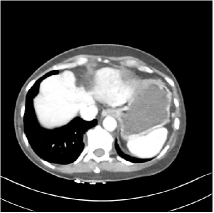

Refer to caption WavResNet [11]Refer to caption WavResNet [11]Refer to caption WavResNet [11]Refer to caption Momentum-Net (SimpleCNN)Refer to caption Momentum-Net (SimpleCNN)Refer to caption Momentum-Net (SimpleCNN)Refer to caption Momentum-Net (SimpleCNN-RSN)Refer to caption Momentum-Net (SimpleCNN-RSN)Refer to caption Momentum-Net (SimpleCNN-RSN)Refer to caption Momentum-Net (Dn-RSN)Refer to caption Momentum-Net (Dn-RSN)Refer to caption Momentum-Net (Dn-RSN)Refer to caption ReferenceRefer to caption ReferenceRefer to caption Reference

Fig. 3: Three examples (from top to bottom) of the reconstructed testing images using Momentum-Net with SimpleCNN (the second column), with SimpleCNN-RSN (the third column), and with Dn-RSN (the fourth column). The compared WavResNet denoised images are shown in the first column, and the reference images are in the fifth column. See their FBP images in Fig. 4.

Fig. 2 shows that the proposed Momentum-Net with SimpleCNN decreases RMSE dramatically in the first 30 layers, and tends to converge in 50 layers. The Momentum-Net reduces the mean RMSE value by 4.5 HU and gives smaller standard deviations in RMSE, compared to WavResNet, as reported in Table 1. This implies that the proposed Momentum-Net with SimpleCNN can improve both the accuracy and stability of low-dose CT image reconstruction than a state-of-the-art image denoising deep NN, WavResNet. The proposed Momentum-Net with SimpleCNN better removes noise and streak artifacts than WavResNet. It also provides clearer reconstructions of some details; see, in Fig. 3, the boundaries shown in the zoomed region at the top-right corner in the first example, the arrow pointed structures in zoomed areas of the second example, and the arrow pointed tissues in the left zoomed region in the third example.

3.3 Momentum-Nets involving RSN-based training